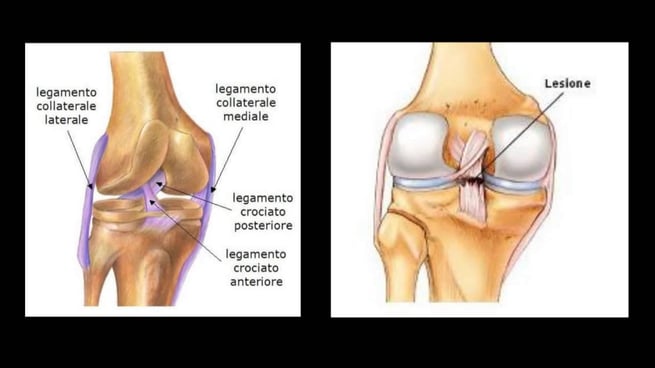

E' importante capire i segni e trattamenti di questa lesione, così come imparare a prevenirla. Il ginocchio è un'articolazione complessa formata dalla rotula, dalla cartilagine e dai legamenti che collegano il femore alla tibia. Questi componenti permettono all'articolazione di funzionare correttamente. Il ginocchio ha due legamenti stabilizzanti essenziali che si incrociano tra loro all'interno del ginocchio: il crociato craniale (o anteriore) e caudale (o posteriore). Il malfunzionamento di anche una sola parte del ginocchio può causare un elevato grado di disagio e zoppia. Dei tanti infortuni che possono verificarsi al ginocchio, la lesione del crociato è tra le più comuni.

La rottura del crociato non sempre può essere prevenuta, ma il rischio può essere ridotto mantenendo il vostro cane ad un peso ideale e sottoponendolo a un giusto esecizio fisico. Una lesione al legamento crociato è il risultato di una rottura parziale o completa. Il legamento crociato craniale è quello più comunemente colpito, anche se il caudale è più sottoposto a rompersi. In caso di lesione al legamento crociato, la tibia si muove liberamente sotto al femore, con conseguente dolore e andatura anomala. Una zoppia improvvisa in una zampa posteriore è spesso il primo segno di lesione. Se la lesione non viene trattata, i problemi artritici possono iniziare molto rapidamente, provocando zoppia a lungo termine e disagio. Se il vostro cane mostra segni di dolore o zoppia, è consigliato far esaminare il vostro cane da un veterinario entro un paio di giorni.